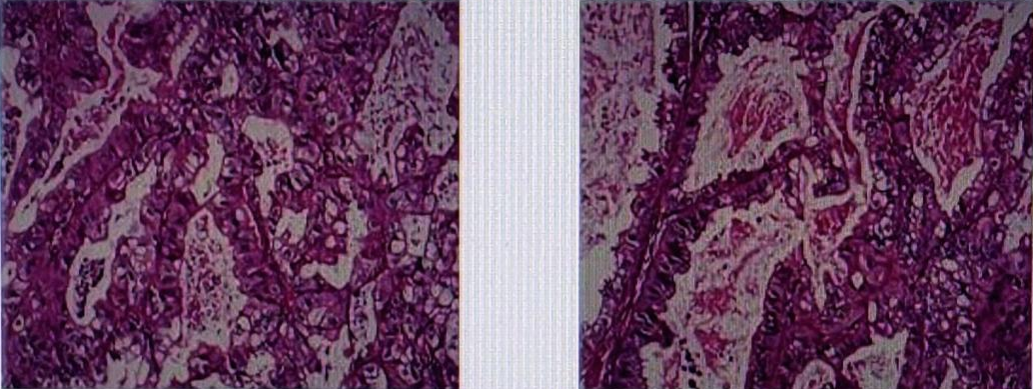

术后病理提示(图3):胃中分化腺癌累及胃壁全层,伴小弯侧淋巴结8/14枚癌转移(可见脉管内癌栓,未见神经侵犯),两断端、大弯侧淋巴结4枚及第4组淋巴结1枚未见癌。

免疫组化结果显示:Her-2(3+),Ki67(20%),CK8/18(+),CDX-2(-),VILLIN(+),CD20(-)

图3. 胃癌术后组织病理切片

术后病理提示(图4):右肺中叶转移性腺癌,考虑来源于胃。支气管旁淋巴结1枚未见癌转移;送检第2、4组淋巴结4枚,第7组淋巴结9枚,9组淋巴结2枚,10组淋巴结4枚,11组2枚均未见癌。

免疫组化结果显示:CK(+),Ki67(10%),CK8/18(+),TIF-1(-),NAPSIN A(+),CK7(+),CK5/6-,P40-,SYN-,CGA-,CD56-,CDX-2-,CK20-。(患者因自身原因术后未行HER2检测)于2021年3月补充免疫组化:Her-2(3+)。

图4. 胸腔镜右肺术后组织病理切片